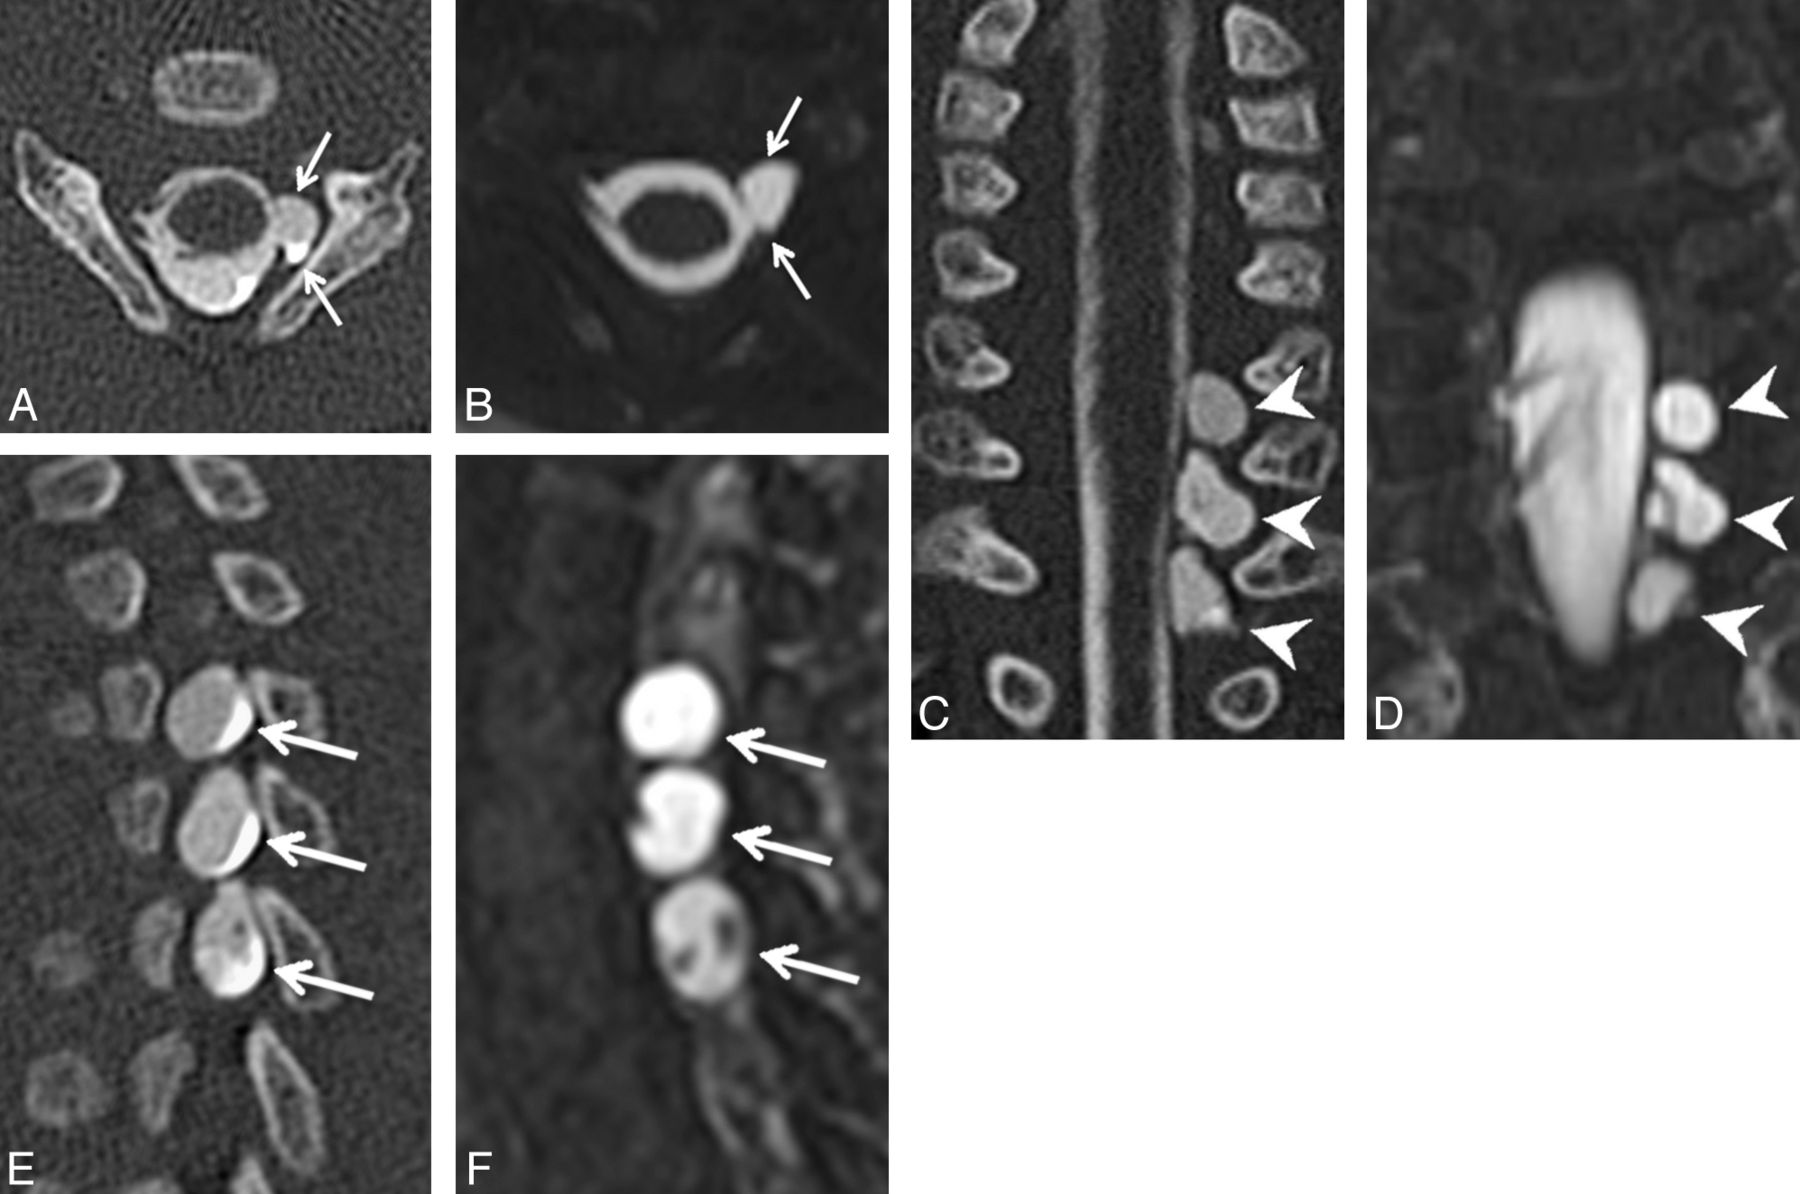

Two pediatric radiologists (with 7 and 8 years' experience, respectively) independently evaluated each imaging study and rated each root level from C5 to T1 according to the system in Table 1. Discrepancies were resolved by consensus analysis. Findings A and B (Figs 1 and 2) have previously been used as predictors of nerve root avulsion in infants.14 Finding C (Fig 3) has been described as a predictor in adults.19 Findings D and E (Figs 4 and 5) have been suggested to indicate partial nerve root avulsion.12

Coronal minimum-intensity-projection image from an MR myelogram demonstrating thinned left-sided ventral rootlets at C6 and C7 (arrowheads), relative to the normal fan-shaped right-sided ventral rootlets on the contralateral side at the same levels (arrows). Base resolution was 0.6-mm isotropic, with a 2-mm minimum-intensity-projection slab.

Coronal (A) and right parasagittal (B) images from a CT myelogram and the coronal (C) and right parasagittal (D) images from the corresponding MR myelogram demonstrating a thickened ventral rootlet at C8 on the right (arrows in A through D). Note that the dorsal rootlet at C8 is thinned. Normal caliber ventral and dorsal rootlets at C7 (arrowheads in B and D) are visible for comparison.